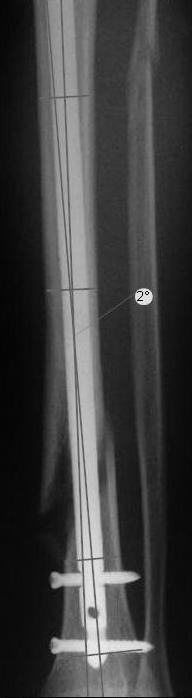

Вы бы стали оперировать или рекомендовали бы своему родственнику оперироваться из-за 2 градусов?

Динамизировать, выкрутив проксимально все винты, на сроке 8 недель ихмо достаточно.